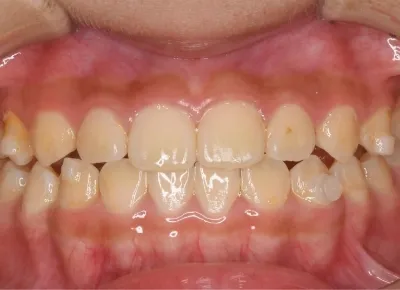

Before

After

治療期間

費用総額